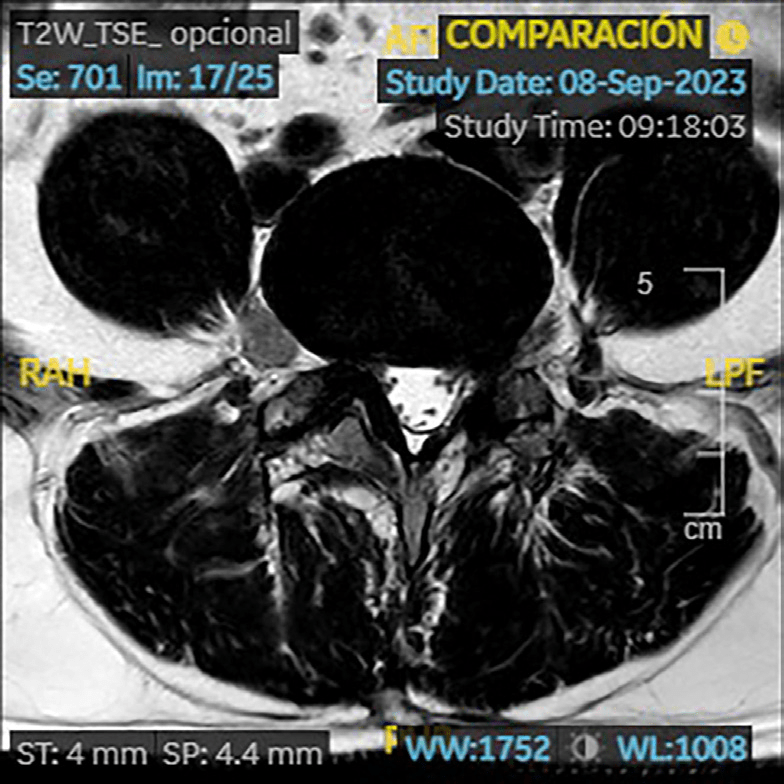

RM (09/2023): cambios postquirúrgicos en L4/L5 con signos de sobrecarga mecánica en platillos vertebrales. Estenosis severa de forámenes neurales L4/L5 por hipertrofia de facetas articulares y por patología discal. Patología en el nivel adyacente L3/L4 con discopatía sin hernia y artropatía degenerativa que producen estenosis moderada foraminal bilateral.

En localización extraforaminal derecha L4/L5, engrosamiento focal sólido de la raíz L4 que mide 15 mm de diámetro y que se realza de forma homogénea tras la administración de contraste intravenoso; sugestivo de tumoración de estirpe neural, neurinoma o neurofibroma.

Schwannoma L4 ho.

La RM de control confirma desaparición de neurinoma.